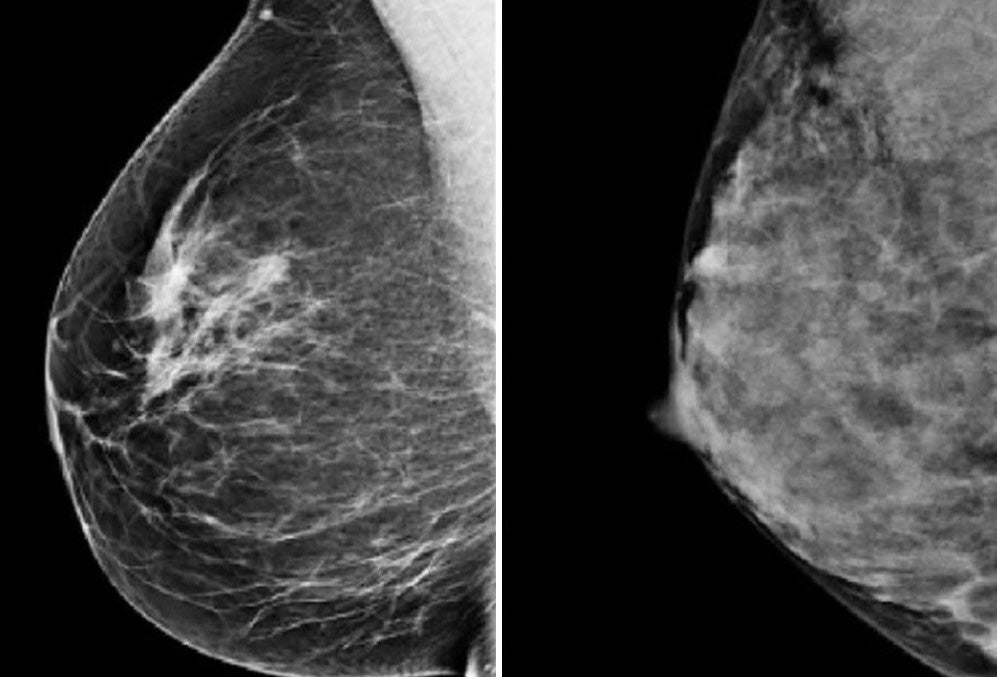

Dense breasts, occurring in about 10% of women, contain more fibrous and glandular tissue and less fatty tissue, obscuring potential tumours during standard mammograms. Women with this type of breast tissue already face a four times greater risk of developing breast cancer.

At the moment, because denser breasts look whiter on mammograms, the usual mammogram scan cannot pick up all these cancers.

Early-stage cancers also appear white, meaning they are difficult to distinguish.